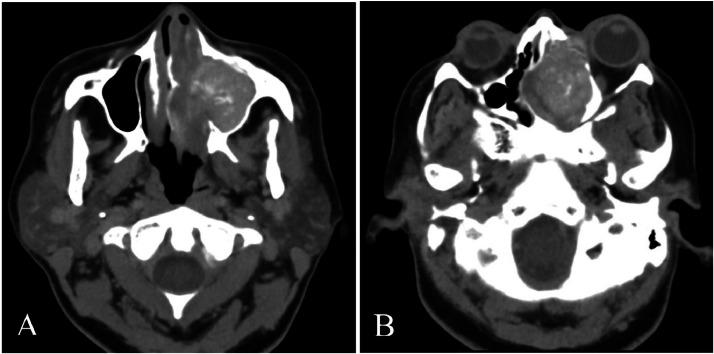

酷似假瘤的慢性侵袭性真菌性鼻窦炎:一例报告。

Chronic invasive fungal sinusitis mimicking pseudotumor: A case report.

Fungal sinusitis encompasses a wide range of diseases, including both invasive and noninvasive, acute, and chronic forms. The incidence of invasive sinusitis is on the rise, primarily affecting immunocompromised individuals and diabetics. This case report highlights a patient who developed invasive fungal sinusitis despite no other apparent cause of immunosuppression. Imaging studies suggested the diagnosis, confirmed by presence of on mycological culture.

摘要

真菌性鼻窦炎涵盖多种疾病,包括侵袭性和非侵袭性、急性和慢性形式。侵袭性鼻窦炎的发病率正在上升,主要影响免疫功能低下的个体和糖尿病患者。本病例报告重点介绍了一名患者,该患者尽管没有其他明显的免疫抑制原因,但仍患上了侵袭性真菌性鼻窦炎。影像学检查提示了诊断,真菌培养发现真菌确诊。